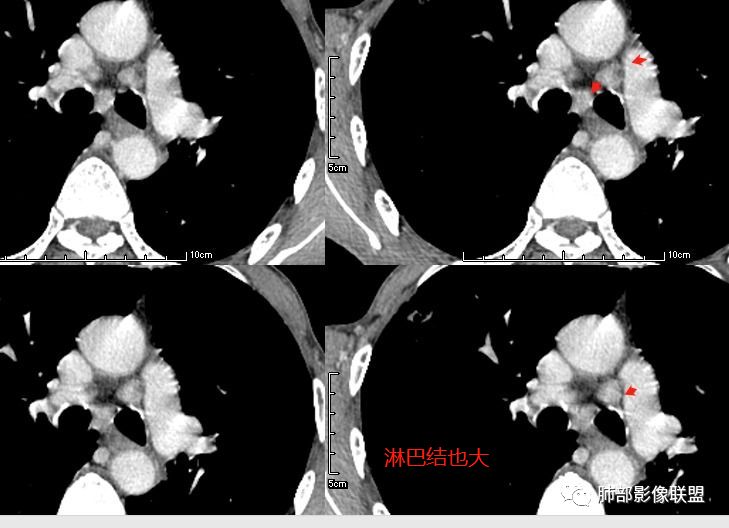

无发热,其他慢性细菌先不考虑,有的低毒的,但是结节形态还是比较不规则的,分布也是比较随机,更像原发病灶。真菌方面,结节没有融合,坏死也是液化坏死,不符合隐球菌,曲霉不符合IPA,慢性吸入的也少见。结核没有树丫,不考虑。鉴别主要是GPA,和肺癌。GPA不支持点是皮肤,肾脏没有累及,ANCA不支持。。。肺癌主要是腺癌和鳞癌转移。比较支持的是淋巴结肿大,和左下肺的主病灶,支气管堵塞和异常强化。还有分叶,局部膨隆。可以建议支气管镜检测。

@曹冠杰,济医附院 GPA一般不会伴有淋巴结肿大,但在继续感染的时候可以有炎性反应性增生。再就是GPA不会出现叶间裂多个结节样改变。

本病例左肺下叶肿块,有深分叶、毛刺、胸膜牵拉凹陷、支气管截断及纵隔内淋巴结肿大等征象,都均支持病灶为恶性,如腺癌,而且叶间裂的多发结节也提示是腺癌来源可能大;双肺多发结节、肿块,大部分病灶有分叶、毛刺及胸膜凹陷的恶性征象,与原发肿瘤本身的性质有关,所以应该与左肺下叶肿块同源,而且双肺多发病灶内空洞也具有多样性;